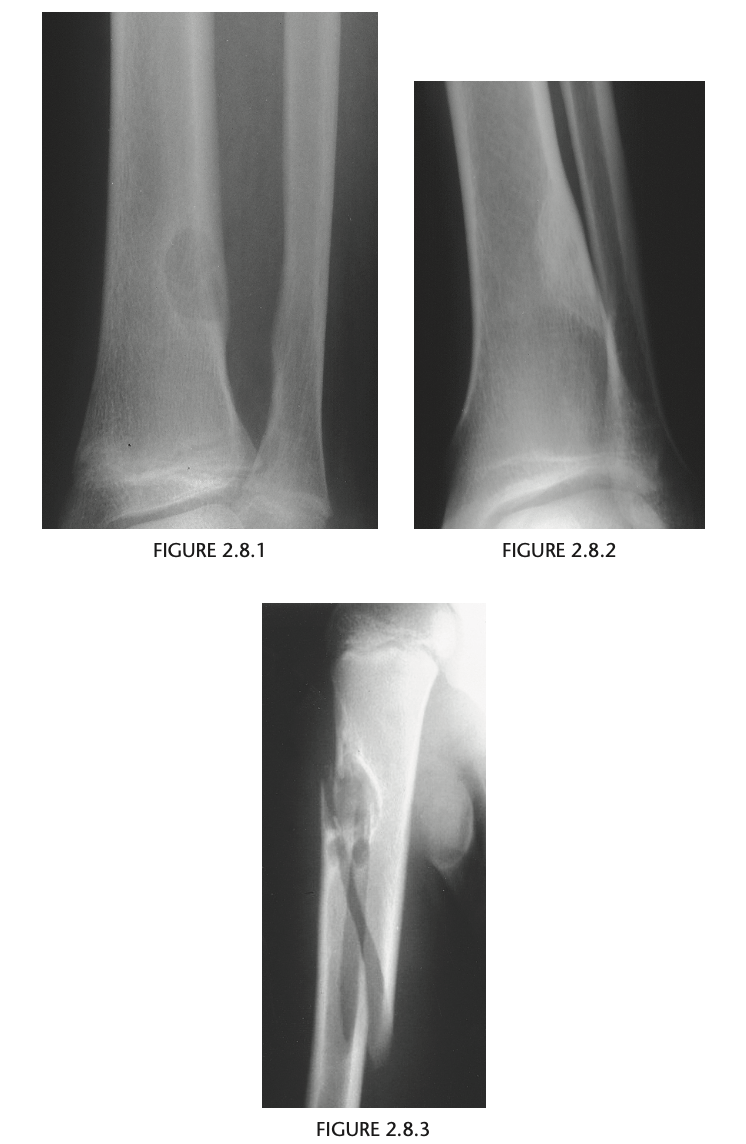

Adolescent child with pain in the leg, another radiograph in the humerus

A

well-defined, eccentric, radio-

lucent lesion with a thin, sclerotic border adjacent

to the cortex of the distal tibia.

Repeat 7 yrs later shows well defined sclerotic lesion in same location.

Humerus radiograph shows identical lesion with pathological fracture

Diagnosis: Fibrous cortical defect or NOF

> 2cm = NOF and <2cm = FCD.

Can be polyostotic - associated with NF, FD, Jaffe-Campanacci syndrome.

Lesions originally

arise adjacent to the physis, and as limb lengthen-

ing occurs, they migrate away from the joint.

typical FCD or NOF is radiolucent; has a thin, scle-

rotic margin; and shows no periosteal reaction.

Rarely, it may be expansile or undergo pathologic

fracture.

Involutes during adolescence and becomes sclerotic.